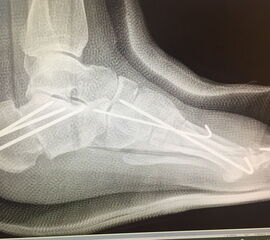

Zusätzlich schränken Wachstumsfugen die Wahl der Osteosynthese ein. Eine die Fuge kreuzende Osteosynthese ist ausschließlich mit Kirschner-Drähten möglich (Abb. 3).

Abb. 3 a-j: Beispiel einer Calcaneusverschiebeosteotomie mit offenen Wachstumsfugen und der entsprechenden Osteosynthese mit Kirschner Drähten. Lokalisation der Osteotomie (a), Lage der Fräse (b-d), Drahtlage mehrere Ansichten (e-h), Heilung der Osteotomie 4 Wochen postoperativ und Entfernung der Drähte (i-j).

Zum Lesen der Bildbeschreibung und zur Vollansicht bitte die Bilder anklicken. Bilder: A. Helmers.

Calcaneus-Osteotomie

Die minimalinvasive Calcaneusverschiebeosteotomie bietet eindeutige Vorteile gegenüber dem offenen Verfahren, sodass wir bei Kindern und Jugendlichen nahezu keine offene Verschiebeosteotomie mehr durchführen. Am Calcaneus liegt die offene Wachstumsfuge dorsal. Bei der Durchführung müssen Schenkel der V-förmigen Osteotomie daher etwas steiler angelegt werden, in einem stumpfen Winkel (siehe Abb. 3 a-j). Für die Osteotomie liegen unsere Patienten auf dem Rücken und der BV wird für die exakte Seitaufnahme eingestellt. Der Fuß lagert auf einem hohen OP-Kissen und die Osteotomie kann bequem mit einem langen Kirschner-Draht und einem sterilen Stift angezeichnet werden (Abb. 15).